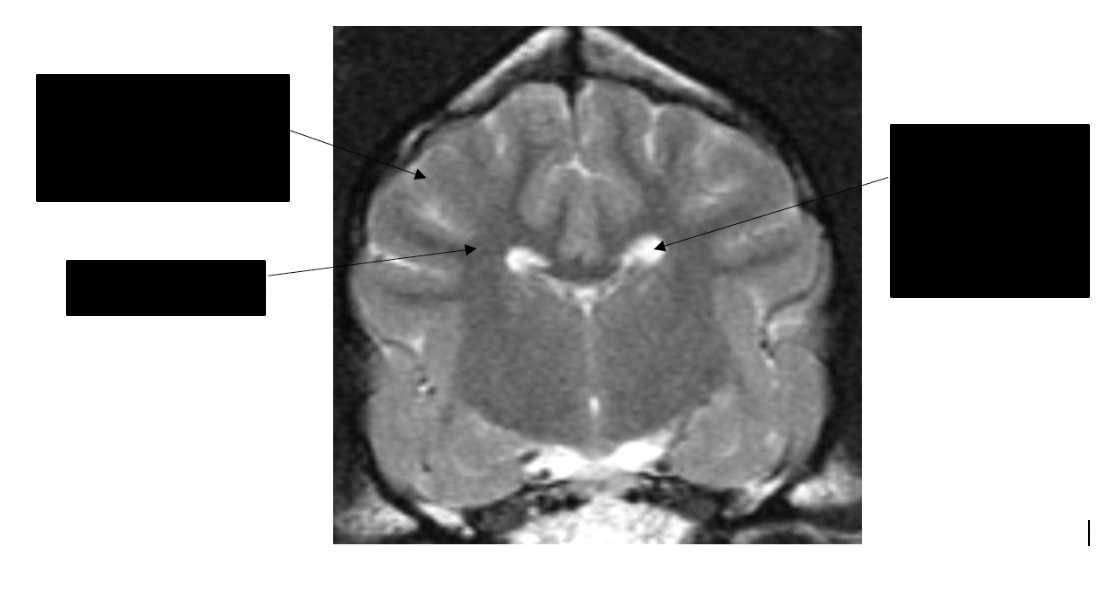

what structures are shown here

internal capsule

corona radiata